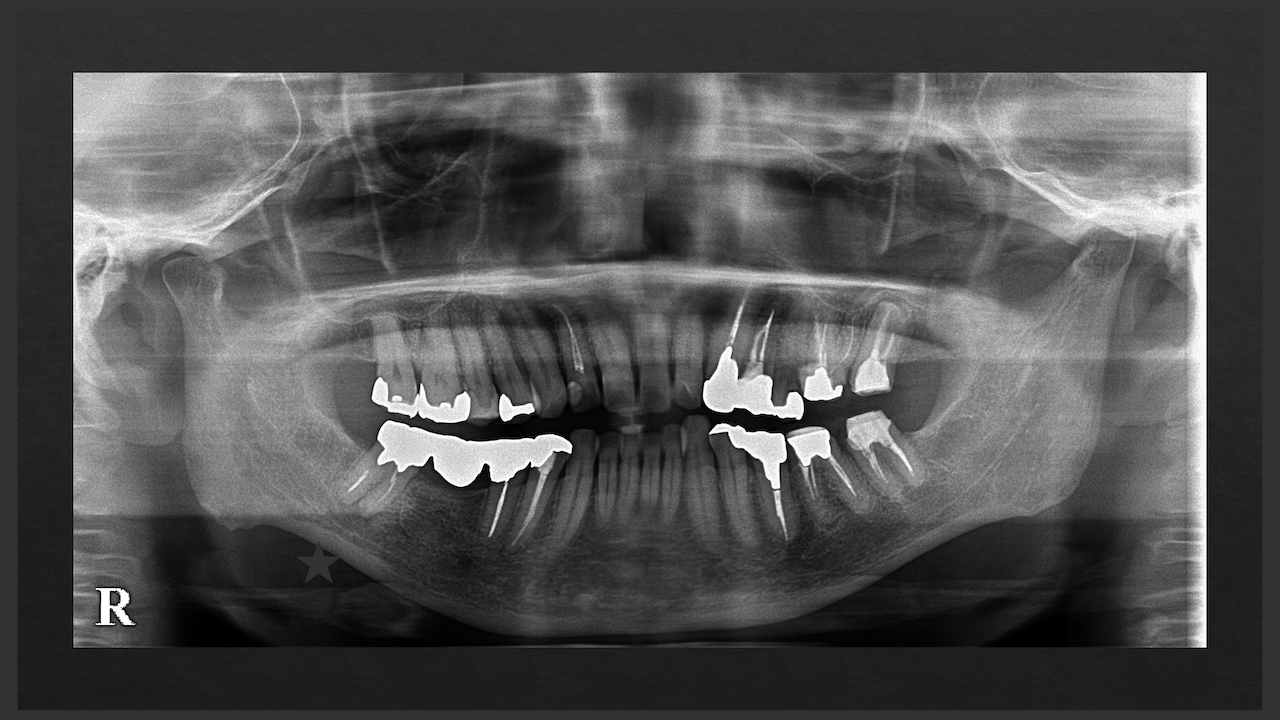

次は横浜からお越しのF先生。

口腔外科出身で外科治療が好きな?先生だ。

Sinus tractがある歯牙の再根管治療だ。

DB根はすでに切断されている。

が、逆根充がなされていない。

DBは根切済みだ。

Pにも病変がある。

ということは、再根管治療だろう。

ただ、予後はGuardedだ。

なぜか?根切がうまく行っていないからだ。

臨床的にDB

この後、

Sinus tractは消失した。

3ヶ月経過した。

DBの病変が小さくなっている。

Pは病変が大きくなっていうように見えるがまだわからない。

ということで、切ることだけが全てでないということを証明してくれた。

このまま経過を追いましょう。

また、Advanced 2026でその結果を教えてください。